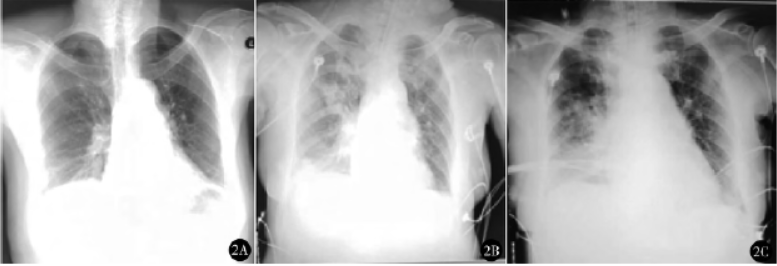

胸片(图1A)、超声心动图等辅助检查未见明显异常。B超示胆囊增大约11 cm×4.6 cm,CT示胆囊结石、胆囊体积增大、部分肠管积气。术前留置胃管,禁食12h,禁饮8h。入手术室,监测血压128/90mmHg,心率93次/min,脉搏氧饱和度(SpO2)95%,负压吸引器抽吸胃管并连接引流袋,面罩给氧去氮,依次静注丙泊酚90mg、依托咪酯16mg、舒芬太尼15μg、罗库溴铵50mg行快诱导插管。在面罩辅助通气过程中,右侧口角流出胃内容物,立即将头部转向一侧,同时将手术台从平卧位调至头低脚高位,吸引口咽腔反流物,在Macintosh直接喉镜暴露声门下置入ID8.0气管导管,气管套囊注气,行气管内吸引后接呼吸机控制呼吸,氧合指数(FiO2)100%,潮气量(Vt)560ml,呼吸频率(RR)12次/min,呼气末CO2分压(PETCO2)35mmHg。静脉给予地塞米松10mg,头孢哌酮舒巴坦3g加入100ml生理盐水静脉滴入。纤维支气管镜检查可见气管及右主支气管黏膜附有淡黄色液体,吸出部分分泌物。

手术过程顺利,手术时间95min。出手术室前胸片示双肺渗出性病变,心影饱满,左侧少量胸腔积液(图1B);动脉血气分析pH值7.43,PaCO2 39mmHg,PaO2 109mmHg,SaO2 98%。带气管导管转入ICU,采用同步间歇指令通气+压力支持通气(SIMV+PSV)模式机械通气24h,静脉注射头孢哌酮舒巴坦(3g,8h一次)抗感染1天,氨溴索化痰等治疗。入ICU后血常规白细胞13.73×109/L,中性粒细胞百分比91.6%。术后第2天拔除气管导管及胃管,转回普通病房。术后第4天胸片示双肺渗出性病变较前吸收(图1C),第5天血常规正常,第10天出院。随访6个月,未见相关并发症。

图1 例1术前胸片(A)提示双肺纹理增多,左上肺硬结灶,左下肺索条影,左侧胸膜增厚;术后即刻胸片(B)提示双肺纹理增多、模糊,可见片状模糊影,肺门影模糊,心影饱满,左肋膈角模糊;术后第4天胸片(C)提示双肺纹理增多、模糊,双肺斑片状模糊影较前减少,右肺门略模糊